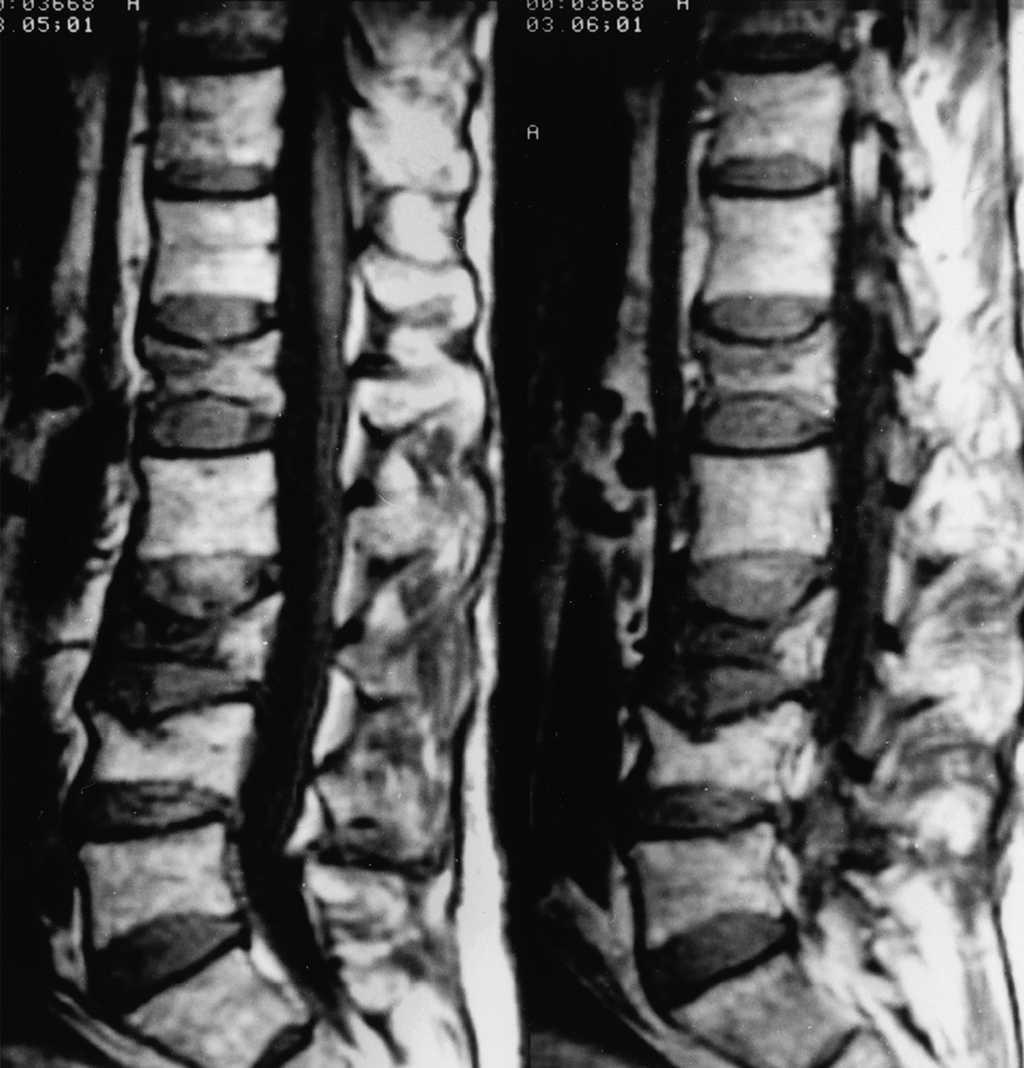

El riesgo de fracturas está relacionado con la dosis y la duración del uso de glucocorticoides, pero se puede observar un mayor riesgo incluso a dosis bajas e incluso en el primer mes de tratamiento.Se recomiendan modificaciones del estilo de vida y la optimización de la ingesta de calcio y vitamina D para todos los pacientes que reciben terapia con glucocorticoides a largo plazo.    Los bisfosfonatos son los medicamentos de primera línea para pacientes con riesgo de fractura moderado o alto, basados ​​en eficacia comprobada, seguridad y bajo costo. Cleveland Clinic Journal of Medicine Julio 2020